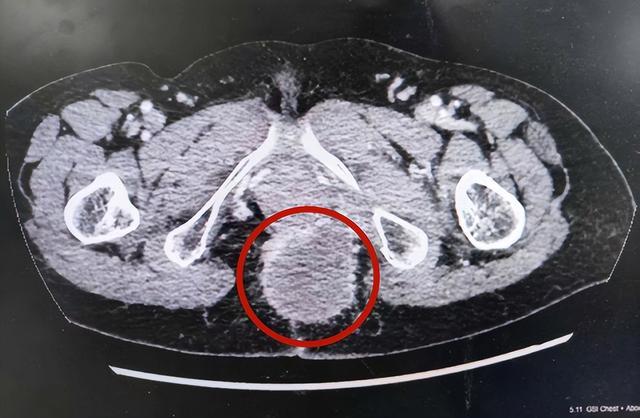

近期,李女士因臀部持续性疼痛来到湖南中医药大学第一附属医院就诊。医生检查发现,李女士会阴部原手术瘢痕处可见橄榄型巨大肿块,长达7厘米,深陷骨盆并嵌顿,浸润双侧肛提肌及阴道壁。

由于患处局部解剖结构极度复杂,与重要脏器毗邻关系密切,手术显露困难、切除难度极大、风险极高。